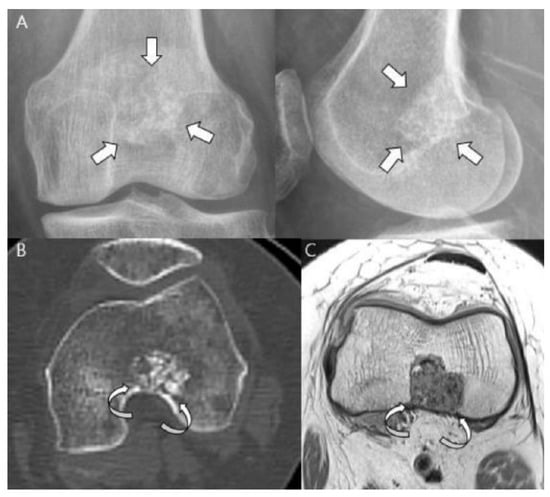

3.3. Distinction between ACT/CS1 and High-Grade Chondrosarcoma

4. Current Treatments and Management